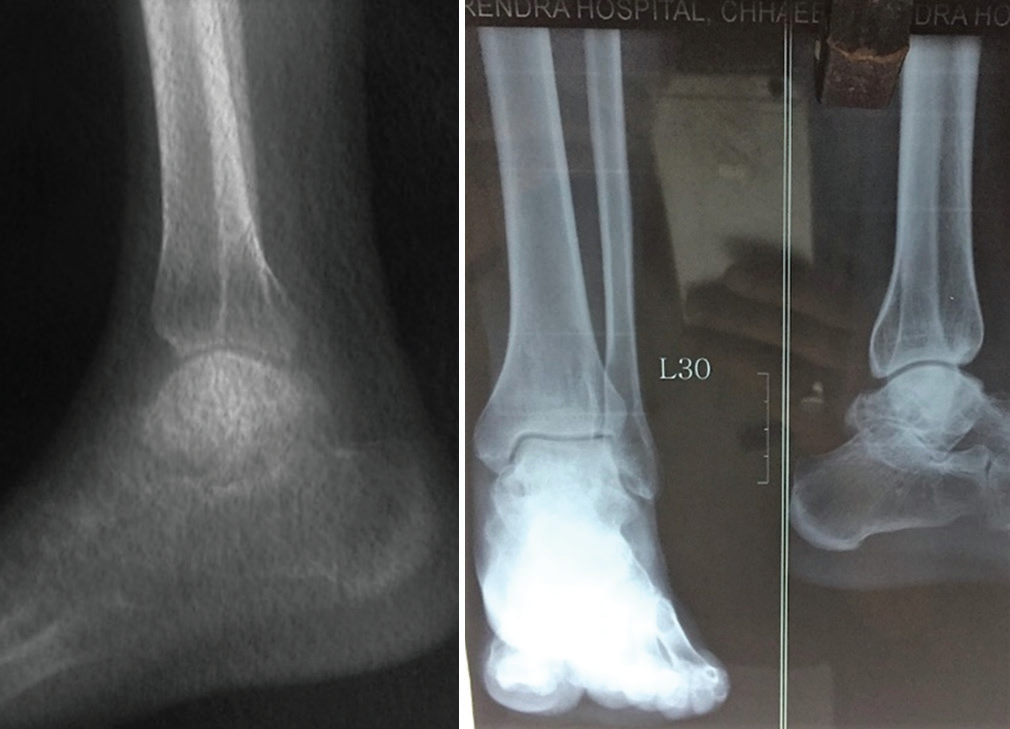

In post-operative period, he was provided with general postoperative care with antibiotic and analgesics. His VAS score for pain was 3/10 in the 7th post-operative day. He was discharged after suture removal in the 2nd week postoperatively and kept under regular follow-up. After surgical intervention, later, he was called on the 6th week postoperatively, 3rd month, 6th month, and 1-year follow-up during which period his pain and discomfort and simple X-ray were [Figures 3 and 4] taken to evaluate graft uptake. His VAS score was 1/10 in the 3rd month, then 0/10 thereafter. It is already more than a year postoperatively and the patient is doing absolutely fine in the last follow-up after a year post-operative.